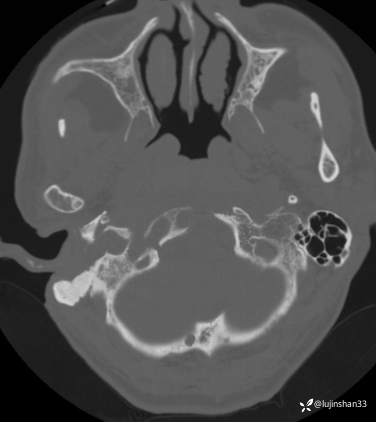

(2023-05-29 16:07,本院)CT颅脑:1、右侧颞骨全切除术后改变,术区见气体密度影,瘘管形成可能;术区多发软组织影,不完全除外炎性改变可能。2、左侧颞骨CT平扫未见明显异常。